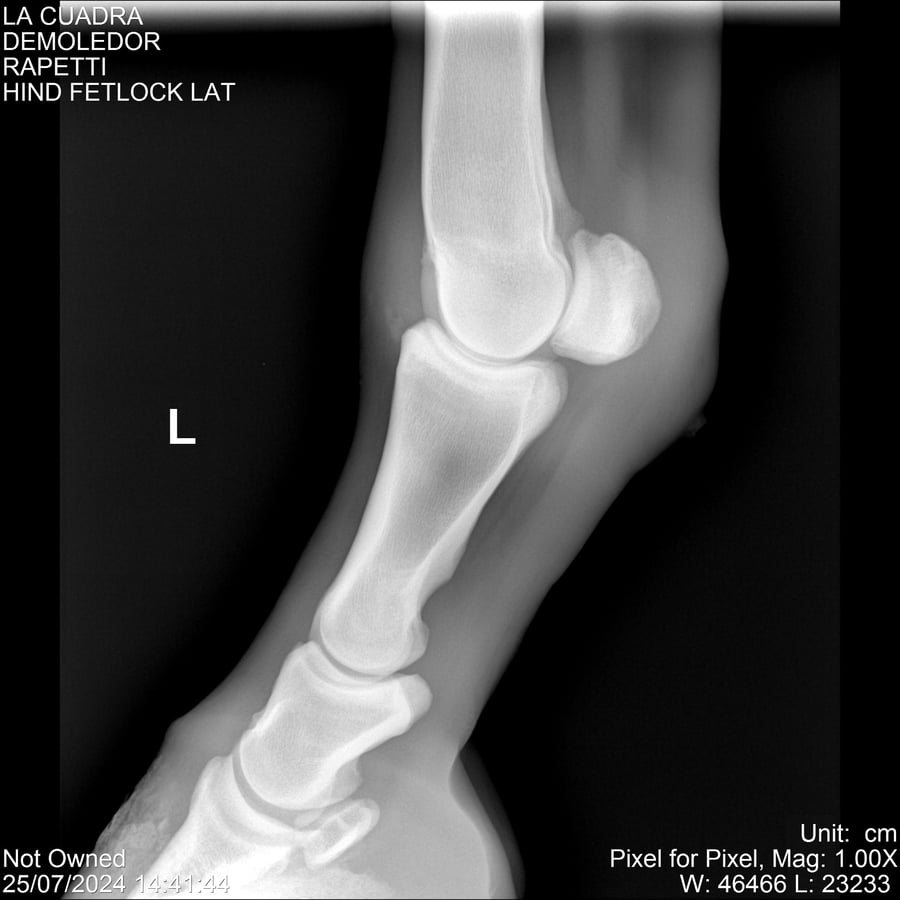

LOTE 14, DEMOLEDOR 🔥 🔥 🔥 Lote Anterior Volver al remate Lote Siguiente Ficha Contacto Montevideo - Ficha del Lote Identificador: #284454 Categoría: Yeguarizos Montevideo - 89 Visualizaciones ClicData Contacto Empresa: Abelenda N. R., Walter Hugo Nombre*: Teléfono* : E-mail* : Mensaje Enviar Registrese gratis Este contenido Exclusivo está disponible sólo para usuarios registrados Ingresar